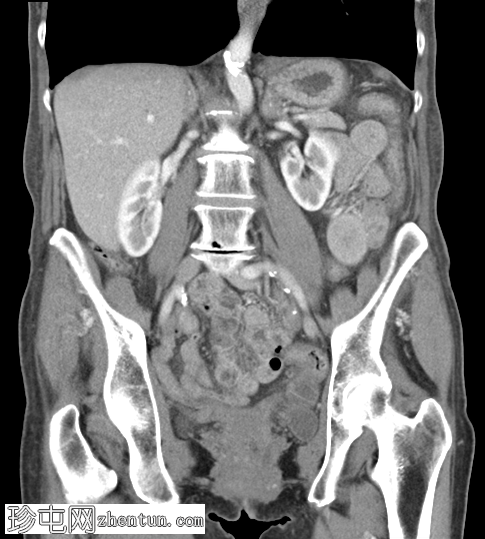

冠状位增强扫描(门静脉期)

可见右侧股疝嵌顿,右侧股静脉受压,输出小肠袢塌陷,输入小肠袢扩张。可见中等量周围游离液体。无缺血征象。右侧努克氏管向内侧移位。疝颈位于腹壁下动脉起始部和腹股沟韧带下方。

肝脏可见多个小囊肿。左侧肾上腺肿大,内含低强化结节。

股总静脉受压、疝颈狭窄、女性、努克氏管向内侧移位、疝颈起源于腹壁下动脉起始部和腹股沟韧带下方等表现,更倾向于股疝而非腹股沟疝。